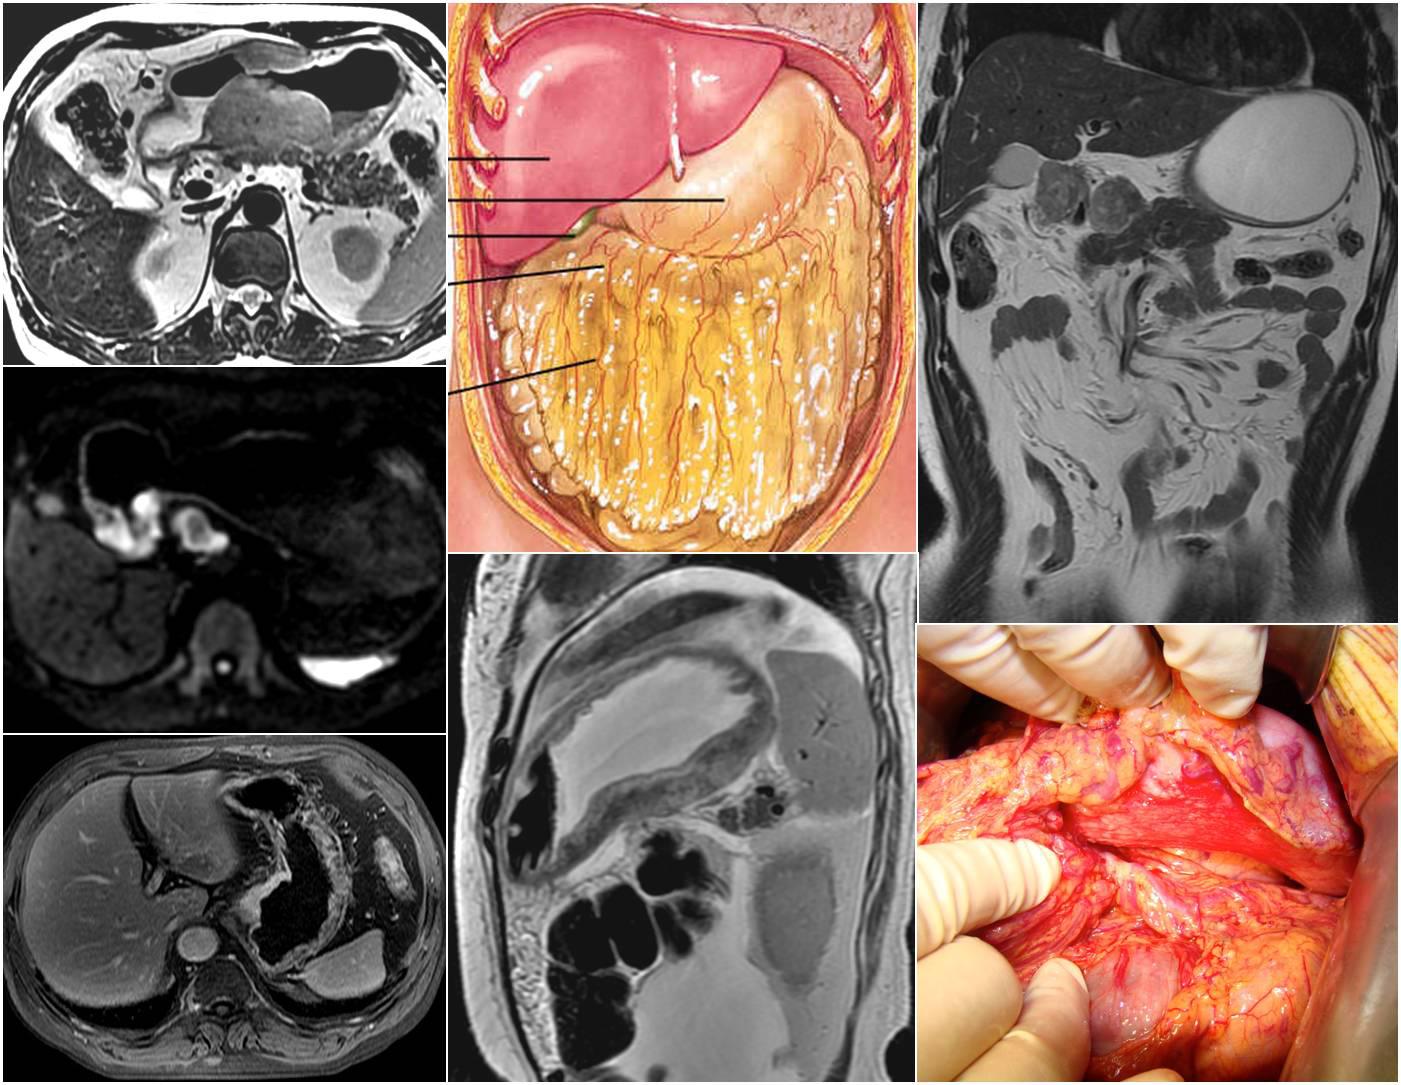

MRI在胃癌的临床应用主要包括分期和疗效评价两个方面。体外MRI高分辨成像(HRMR)可分辨胃壁的5-8层细微结构,展示出MRI优异的软组织分辨能力,对胃癌的精确分期有潜在价值。综合多项文献报道,MRI对胃癌T分期的准确率达到80%以上水平,分期效能略优于CT。各T分期的MRI征象包括:cT1,增强序列显示胃壁无增厚,或增厚的胃壁以粘膜层为主,高强化的黏膜层与等强化肌层间存在低强化黏膜下层;cT2,增强序列显示高强化癌肿累及胃壁全层厚度>50%;cT3,增强序列或FSE T2WI序列显示癌肿累及胃壁全层,浆膜面光滑;cT4a,不抑脂FSE T2WI显示癌肿胃壁浆膜面多发索条毛刺外侵或结节样外突,或浆膜面中断伴胃周脂肪信号减低、层次结构模糊;cT4b,增强序列或FSE T2WI序列显示癌肿侵犯周围脏器,以形成“嵌插征”为较为确切的侵犯征象。非抑脂FSE T2WI还有助于腹膜转移的早期检出,包括“污迹征”、“卷发征”等;以及对横结肠系膜等少见位置的观察。

磁共振成像的另一优势是可提供功能定量指标,目前较为常用的是磁共振扩散加权成像(DWI),其借助水分子扩散速度差异对比,提高胃癌对比显示能力并可提供功能定量参数,在胃癌的生物学行为及疗效评价方面展示出应用前景。目前国内外已有多项预后相关研究证实,DWI可早期预测胃癌放化疗疗效,其量化表征值ADC与病理退缩率及生存相关指标密切关联,有望成为继PET SUV值之后的又一个功能影像学评效指标。且其无辐射损伤,成像经济便捷。